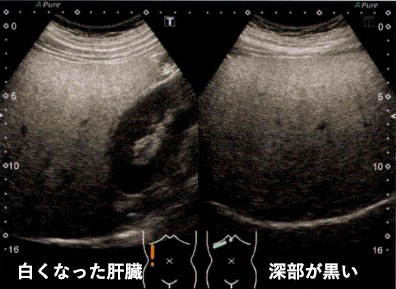

今まで、肝臓の脂肪化は「肝臓が腎臓より白い」「肝臓の深いところが黒い」「肝臓の血管などが見えづらい」といった見た目で評価をしていました。

従来の肝脂肪化評価

見た目で評価

肝脂肪化測定

客観的な”数値“で把握